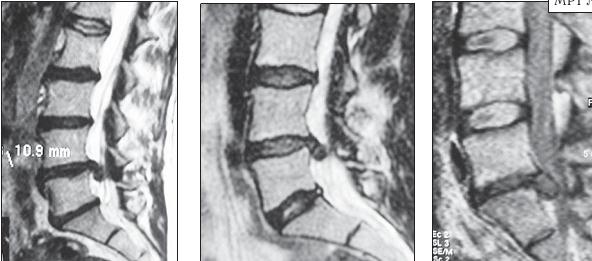

На серии снимков МРТ № 24 наблюдаются дорсальные грыжи межпозвонковых дисков в поясничном отделе позвоночника в сегментах Lv—SI Это самый уязвимый межпозвонковый диск, так как в силу своего анатомического расположения на него приходятся самые большие нагрузки. Как говорится, по счёту «последний», а по уязвимости, первый. Поэтому в нём чаще, чем в других межпозвонковых дисках, возникают, различные осложнения, в том числе и грыжи МРТ № 25

На серии снимков МРТ № 25 наблюдаются дорсальные грыжи межпозвонковых дисков в поясничном отделе позвоночника в сегментах LIV-LV Lv—SI Такие комбинации, в которых образуются по нескольку грыж, межпозвонковых дисков одновременно, случаются довольно часто на более поздних стадиях развития дегенеративно-дистрофического процесса. В общем, беда не приходит одна, «несчастье» любит, компанию МРТ № 26